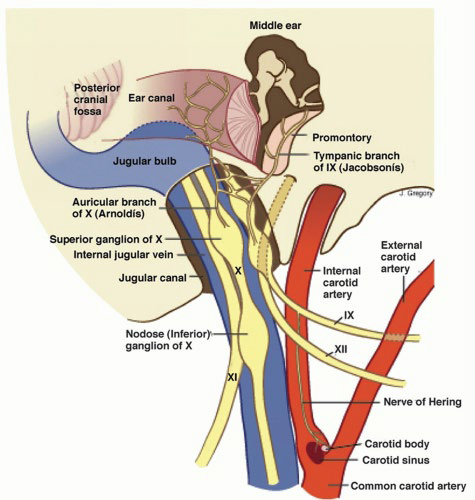

Internal carotid a.

- 進入carotid canal 前無分支

- CN X 伴行

- Carotid canal入顱

- carotid a. 夾 Stylopharyngeus m.(CN IX) , Styloglossus m. (CN XII)

CN IX

Motor

- Stylopharyngeus m.

- Lesser petrosal n.(Parasymphysis)

- 支配Parotid g.的副交感節前神經

Sensor

- Tympanic n.

- 中耳、鼓膜內面、耳咽管(Eustachian)

- Sinus n.

Terminal

- Pharyngeal br.(with CN X)

- Mucosa of oropharynx

- Tonsillar br.

- Palatine tonsil

- Lingual br.

- 舌頭後1/3味覺、一般感覺

分隔ECA,ICA

CN X

Structure

- common carotid a. 外側,蓋在 thyrocervical trunk 上

Sup. cervical ganglion

支配carotid plexus, pharyngeal plexus